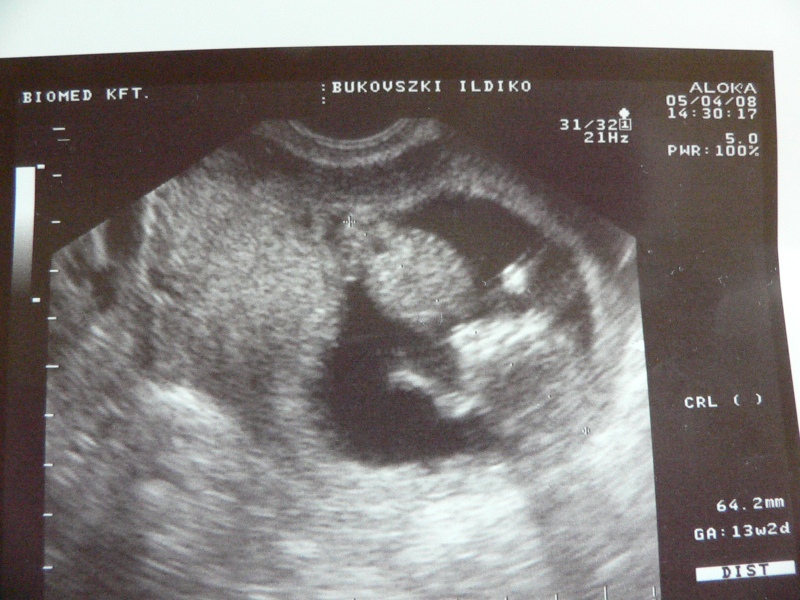

| itt pedig oldalnézetből és a köldökzsinór is látható. | |